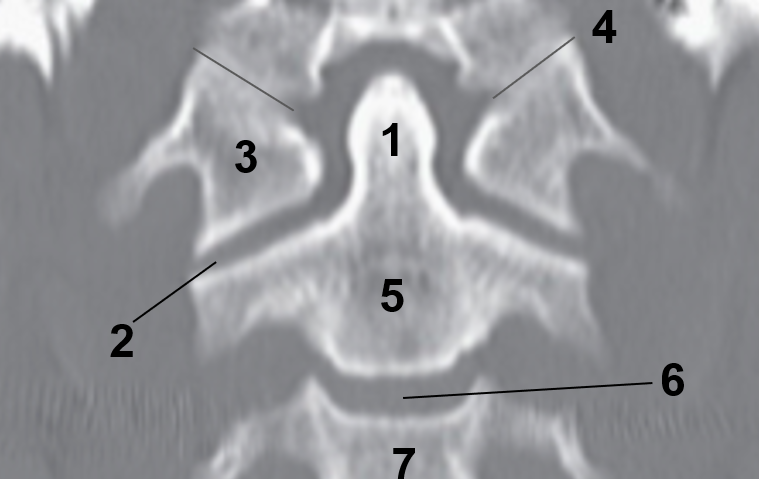

1?

Nasal Bone

2?

Maxillary Sinus

3?

External Acoustic Meatus

4?

Pons

5?

Cerebellum

6?

Mastoid Air Cells

7?

Mandibular Condyles

8?

Sphenoid Bone

9?

Maxillary Bone